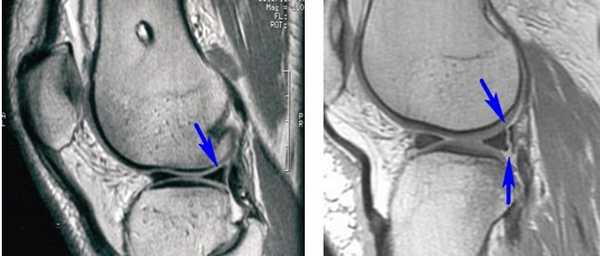

Длительность операции

Длительность хирургического вмешательства обычно зависит от степени повреждения мениска. В среднем артроскопия длится 60 минут. В сложных случаях она может продолжаться 1,5-2 часа. На МРТ справа — разрыв заднего рога мениска, слева — здоровый мениск.